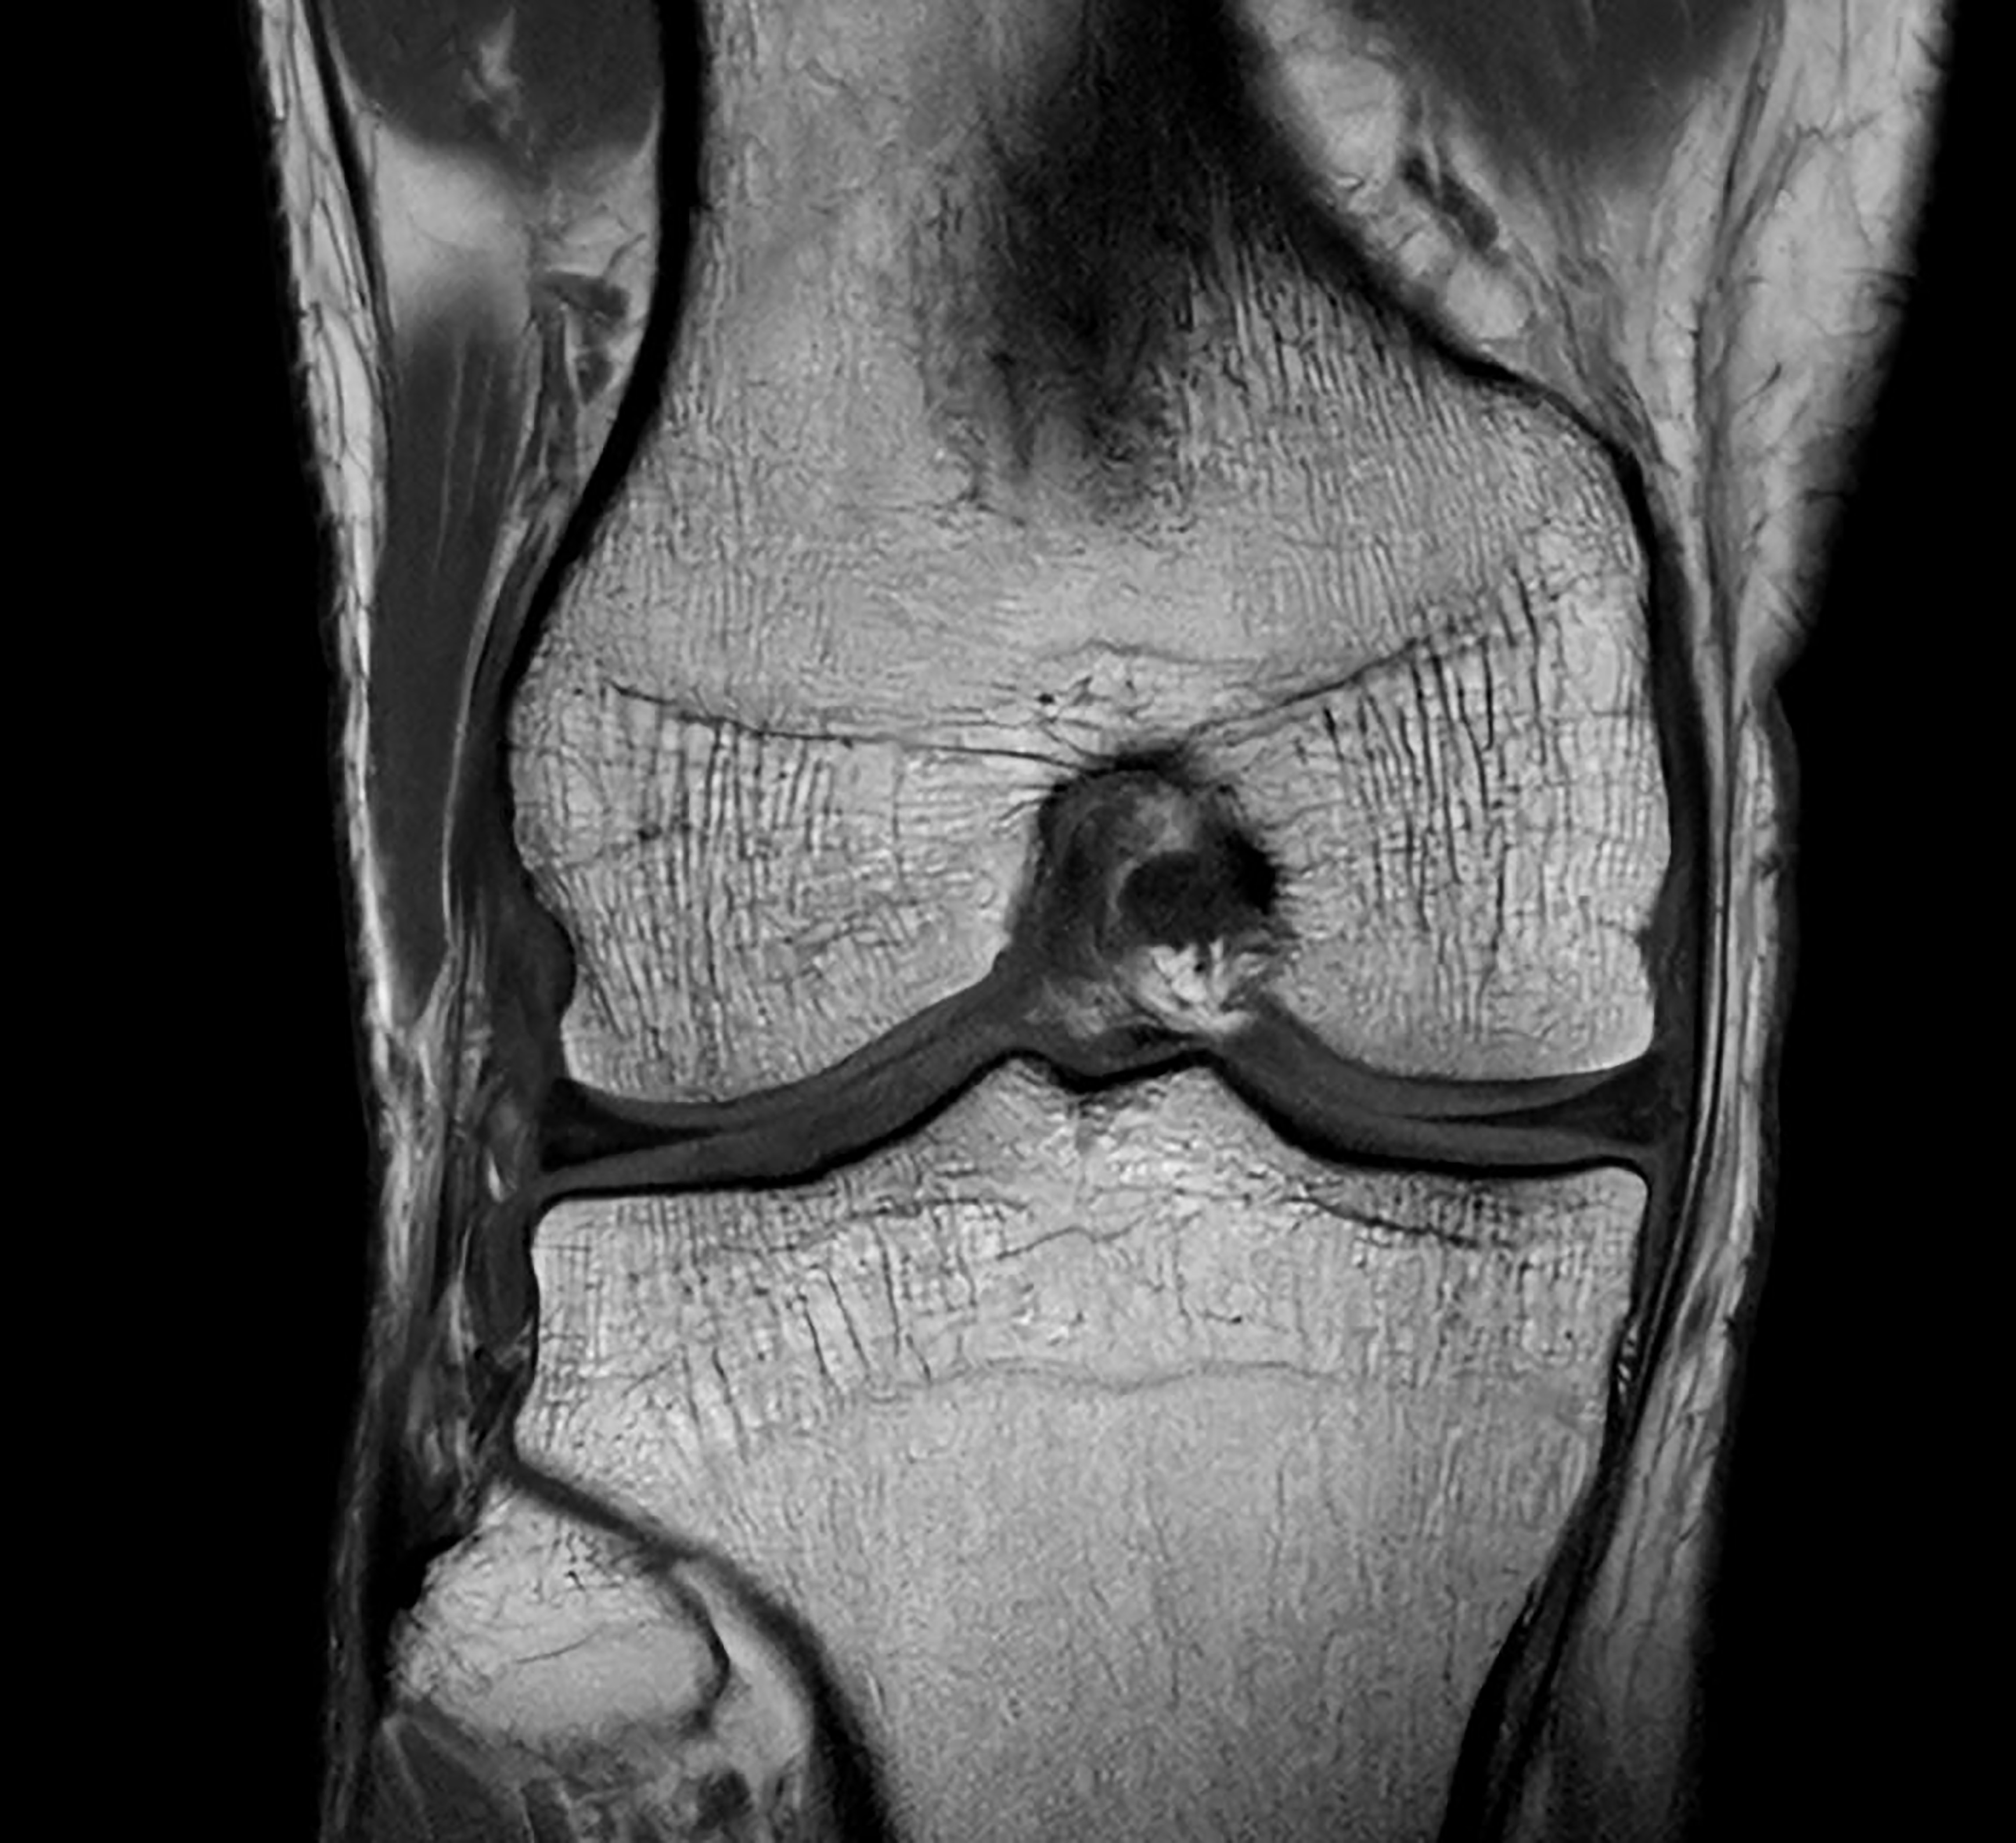

De nieuwste SmartSpeed Precise [1]-technologie verhoogt de productiviteit nog verder, waardoor scans tot drie keer sneller kunnen worden uitgevoerd [7] en de scantijd aanzienlijk wordt verkort terwijl de uitzonderlijke beeldkwaliteit behouden blijft. De kern van SmartSpeed Precise is de dual AI-engine, die zorgt voor een verbetering van 80% in de scherpte van de beelden [8], waardoor de visualisatie wordt verbeterd voor betrouwbaardere en nauwkeurigere diagnoses. Deze krachtige combinatie van snelheid en precisie zorgt ervoor dat radiologen subtiele afwijkingen duidelijker kunnen detecteren, wat uiteindelijk leidt tot betere patiëntresultaten. De nieuwe release van Philips – MR Workspace R12 [6] – introduceert een ‘zero-click’-workflow [9], die het gehele beeldvormingsproces naadloos begeleidt, van het starten van de scan tot het genereren van rapporten. Door handmatige handelingen te verminderen en de efficiëntie te optimaliseren, stelt MR Workspace R12 [6] radiologieafdelingen in staat de patiëntdoorstroming te verbeteren en achterstanden terug te dringen, waarmee tegemoet wordt gekomen aan de toenemende vraag naar snellere en nauwkeurigere beeldvorming. Een belangrijke innovatie binnen MR Workspace R12 [6] is de door AI aangestuurde SmartExam-functie, die 80% van de MR-procedures automatiseert [10], door werkzaamheden te stroomlijnen en beeldvormingsworkflows te standaardiseren.